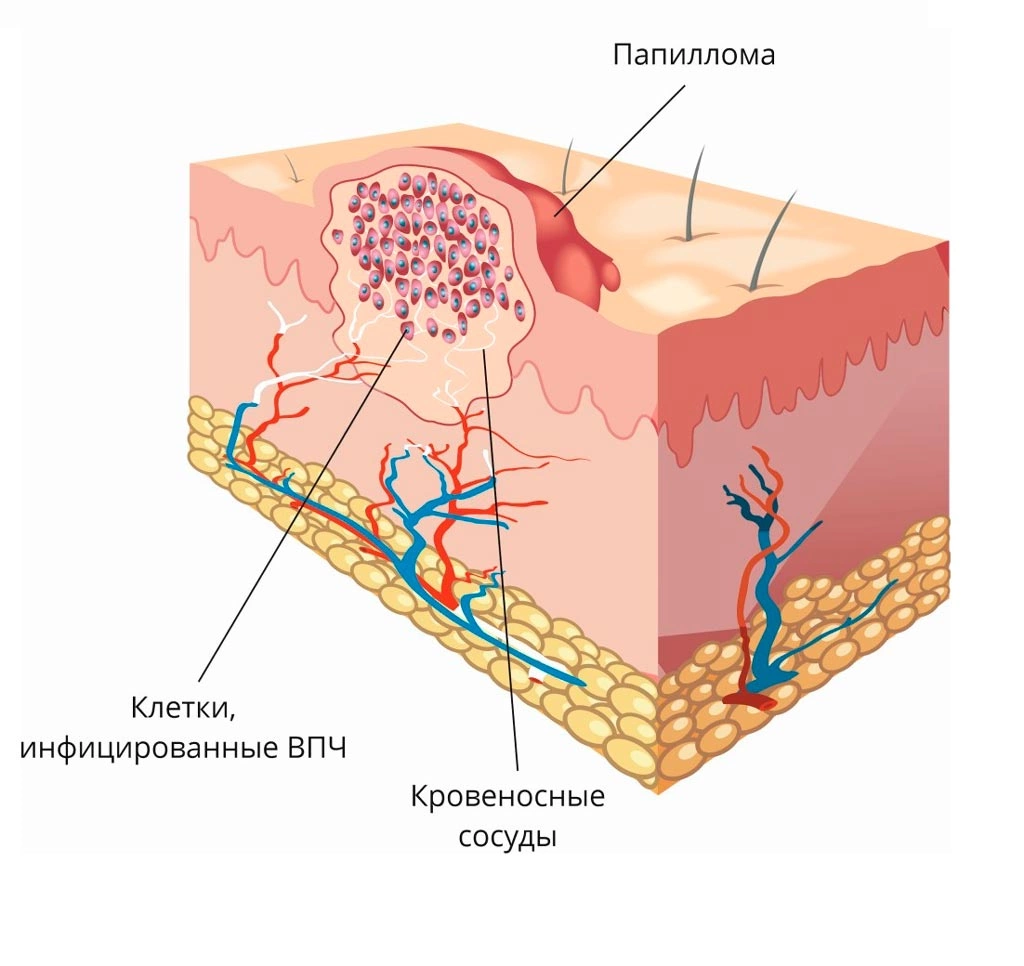

Кондиломы - это одно из самых распространенных заболеваний, передающихся половым путем. Они вызваны вирусом папилломы человека (ВПЧ) и могут появляться на внешних половых органах, анусе, ротовой полости и других областях тела.

Симптомы кондилом могут варьироваться, и визуальное представление этого заболевания может быть различным. Некоторые кондиломы выглядят как небольшие бугорки или бородавки, в то время как другие могут иметь форму плоских пятен или цветных наростов.